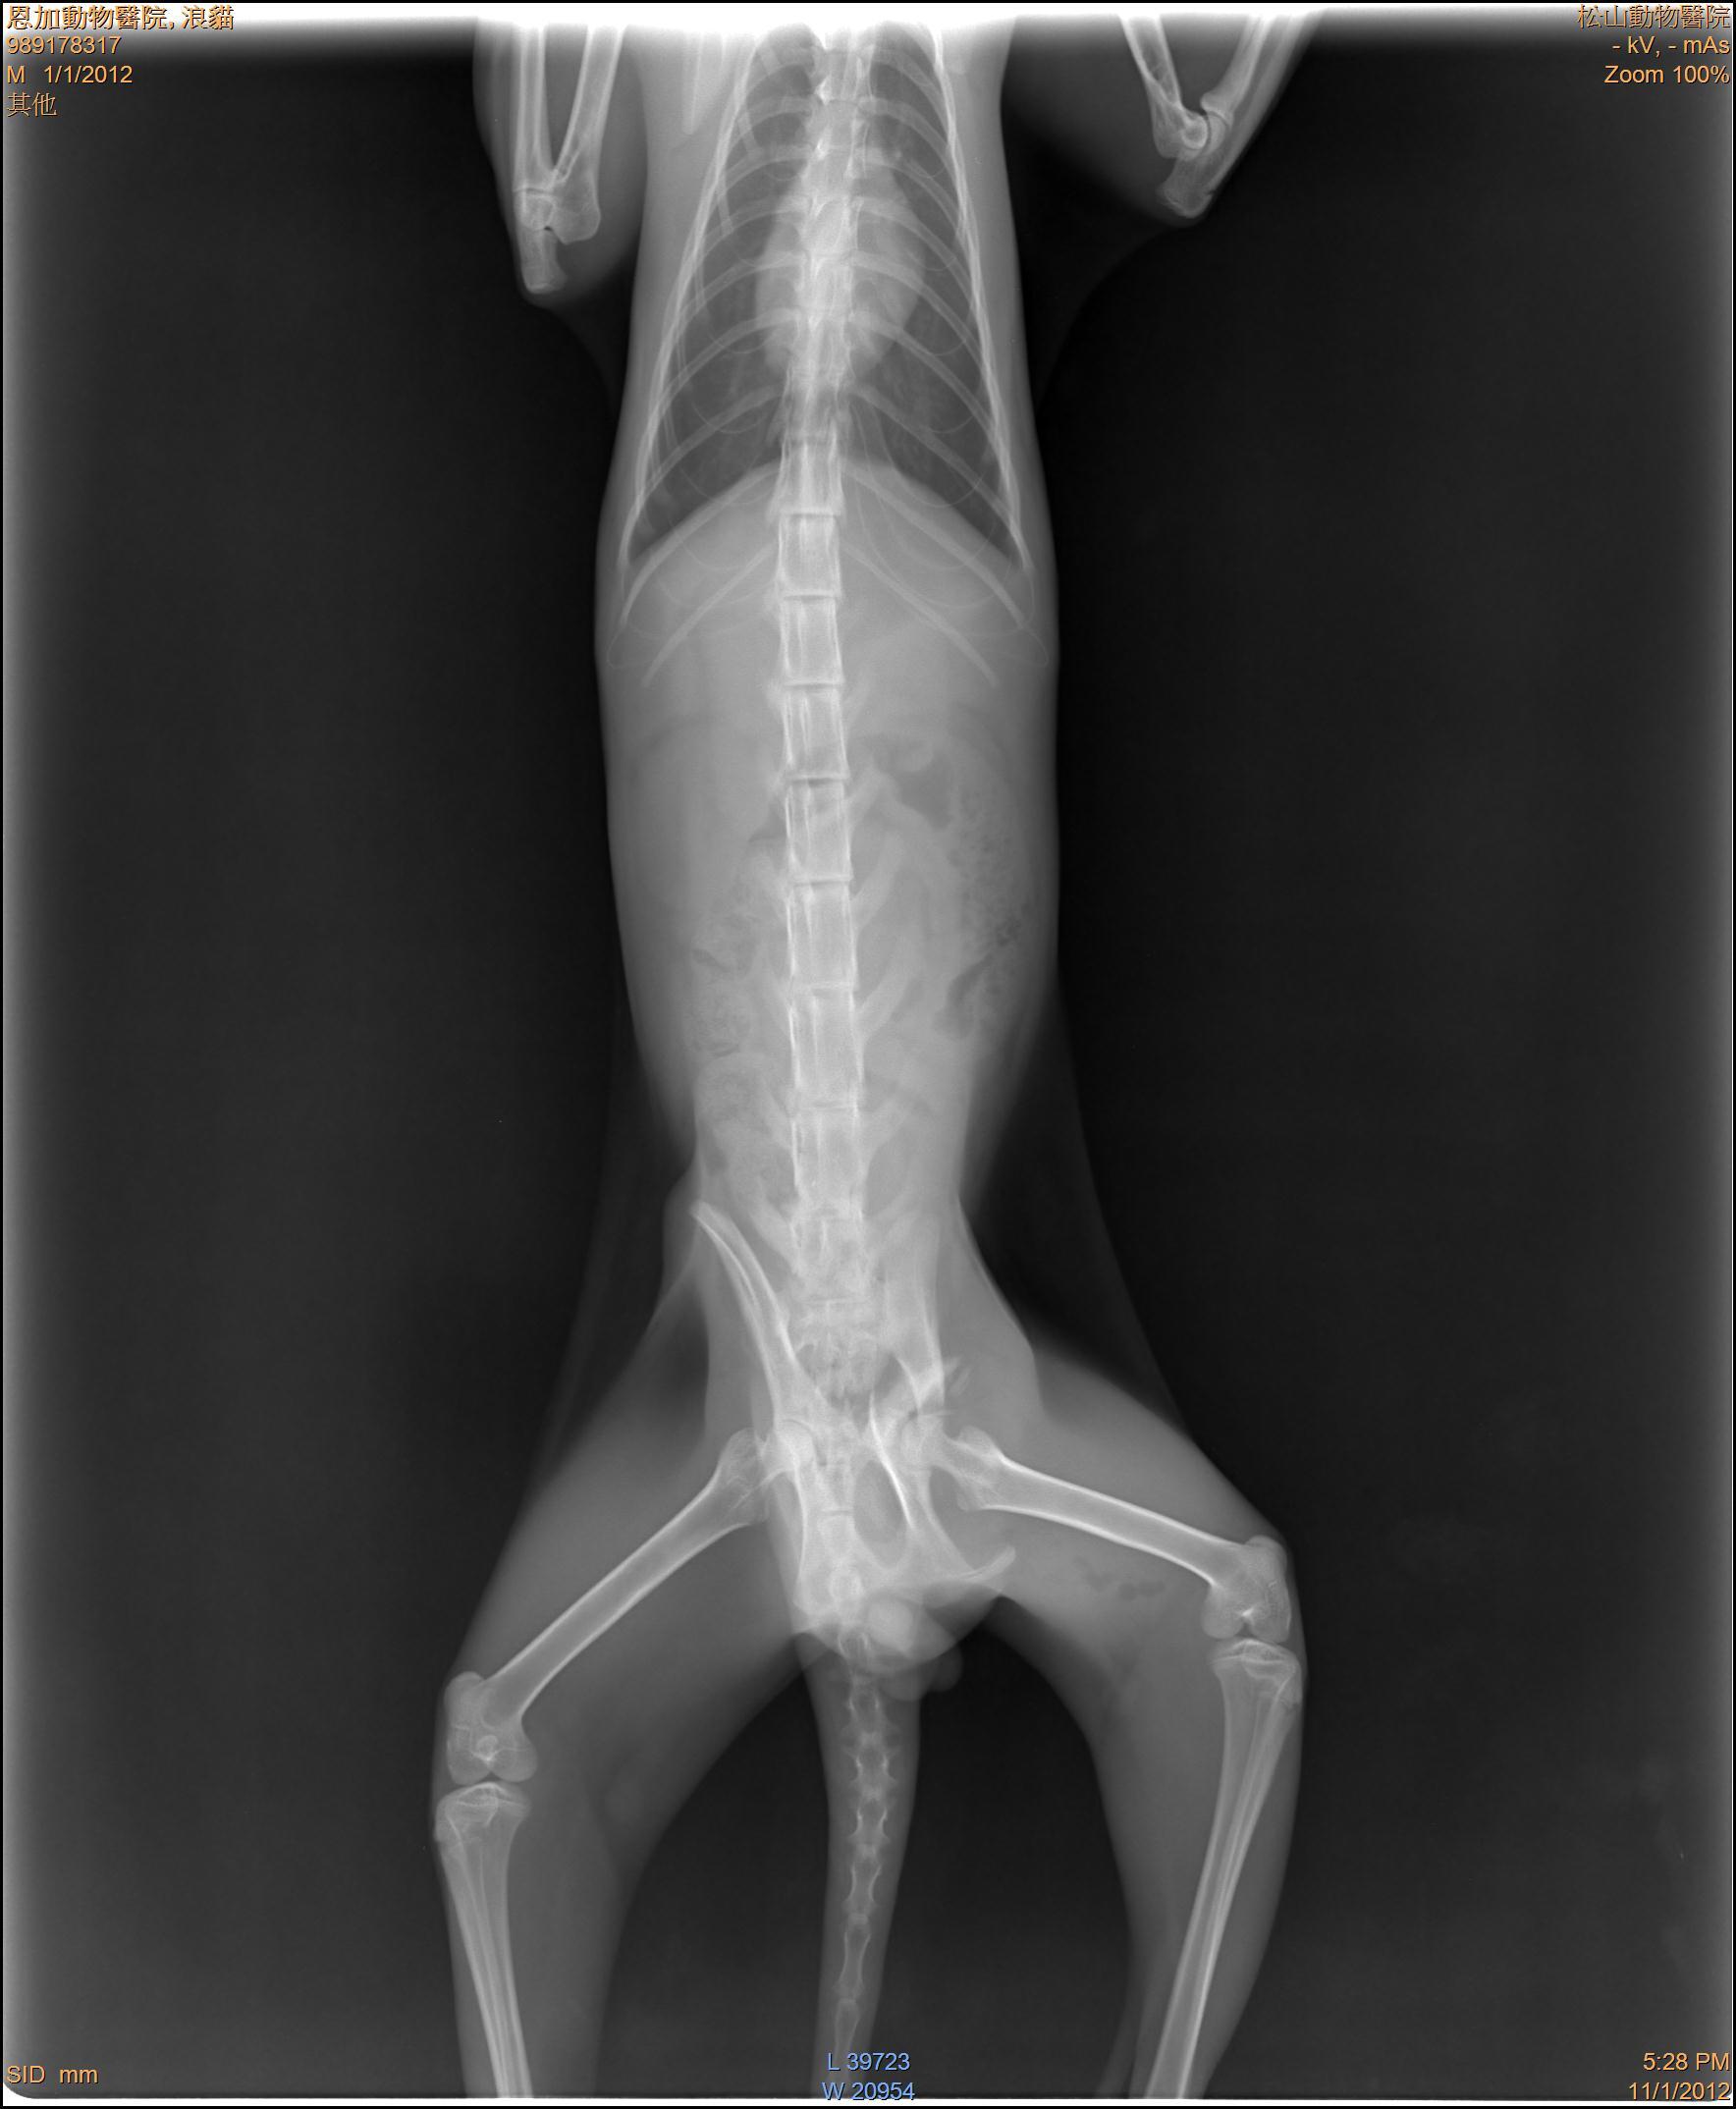

- 編號: 1467

主題: 骨盆受傷跛腳公貓 申請者姓名: 敏大哥 花色: 申請日期: 2012-11-24 16:50:51 申請者部落格: 申請者臉書網址: 所在縣市/合作醫院: 台北市/恩加動物醫院 治療費用: 7100元 需求人數: 16人 已結案 (2013-06-27 14:10:45) 報名人員: Anita Lu、Cherry Hsu(已付款)、Freda Shen(已付款)、Huai-chie Chiue(已付款)、小心(已付款)、盈盈(已付款)、常音(已付款)、Issa Chang(已付款)、mina(已付款)、Dale Peng(已付款)、Coco Ho(已付款)、Edwin(已付款)、Sky(已付款)、Sky(已付款)、Sky(已付款)、Sky(已付款)、Sky(已付款)、 候補人員: 陳宏林、 動物病情說明: 貓友文凡通報到請支持流浪貓TNR粉絲團,此貓在萬華區華中橋端,由我去誘捕帶回醫療,醫生說骨盆有骨折,治療之後發現除了骨盆的問題,還有神經受損的問題因此痊癒後先帶回照顧,看看神經問題能恢復多少,能否恢復行動力。